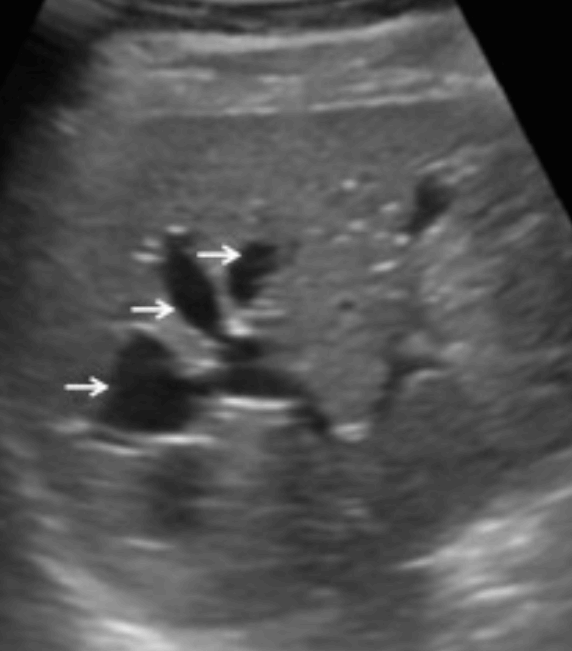

US finding

- 담관과 연결되는 많은 낭포가 있다.

- 담관 내 결석과 반사체가 보인다.

선청성 담관확장증 (Caroli's disease) Benign bile duct disease